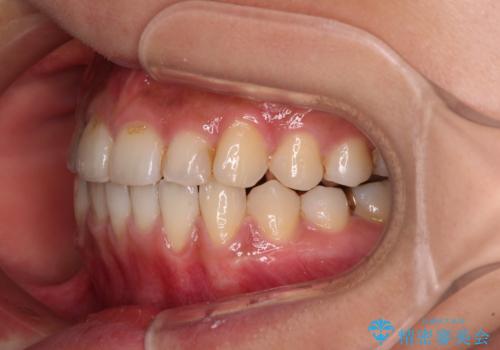

前歯のデコボコとクロスバイト インビザラインによる矯正治療

- 上下のクロスバイトと前歯のデコボコを気にして来院された患者様です。

骨格的に下顎がやや前方にあり、奥歯にクラウンが装着されているため、矯正治療後半の不安定な咬み合わせを避けるのであればワイヤー矯正がおすすめとなりますが、希望によりインビザラインにて治療を行うこととしました。

インビザラインを用い、IPR(歯と歯の間を削る)と歯列全体を拡大させることで、歯並びを整えていくこととしました。

懸念されたとおり、右下のクラウン部分が全く咬み合わず、仕上げの段階で治療期間が長くなりました。